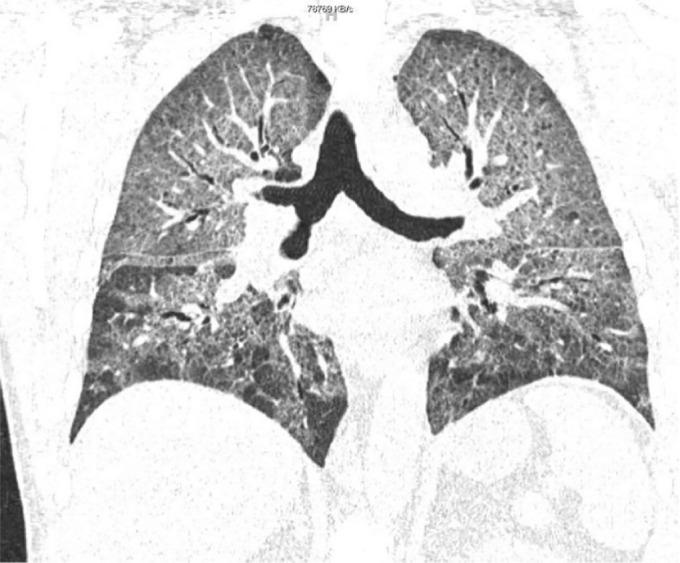

A 56-year-old male with a past medical history of coronary artery disease and chronic obstructive pulmonary disease was admitted for a coronary artery bypass graft. Post-operatively, the patient was admitted to the ICU for ventilator management and continued to receive his home dose of amiodarone 400 mg orally twice daily, which he had been taking for the past 3 months. The patient was found to be hypoxemic with a PaO2 52 mmHg and bilateral infiltrates on chest x-ray. Patient also complained of new onset dyspnea. Physical exam found bilateral rhonchi with bibasilar crackles and subcutaneous emphysema along the left anterior chest wall. Daily chest x-rays showed worsening of bilateral interstitial infiltrates and pleural effusions. A chest high-resolution computed tomography on post-operative day 3 showed extensive and severe bilateral ground glass opacities. APT was suspected and amiodarone was discontinued. A course of oral prednisone without antibiotics was initiated, and after one week of treatment the chest film cleared, the PaO2 value normalized and dyspnea resolved.

APT occurs via cytotoxic T cells and indirectly by immunological reaction. Typically the lungs manifest a diffuse interstitial pneumonitis with varying degrees of fibrosis. Infiltrates with a 'ground-glass' appearance appreciated on HRCT are more definitive than chest x-ray. Pulmonary nodules can be seen, frequently in the upper lobes. These are postulated to be accumulations of amiodarone in areas of previous inflammation. Those undergoing major cardiothoracic surgery are known to be predisposed to APT. Some elements require consideration: a baseline pulmonary function test (PFT) did not exist prior. APT would manifest a restrictive pattern of PFTs. In APT diffusing capacity (DLCO) is generally >20 percent from baseline. A DLCO was not done in this patient. Therefore, not every type of interstitial lung disease could be ruled out. Key features support a clinical diagnosis: (1) new dyspnea, (2) exclusion of lung infection, (3) exclusion of heart failure, (4) new radiographic features, (5) improvement with withdrawal of amiodarone. Our case illustrates consideration of APT in patients who have extensive use of amiodarone and new onset dyspnea.